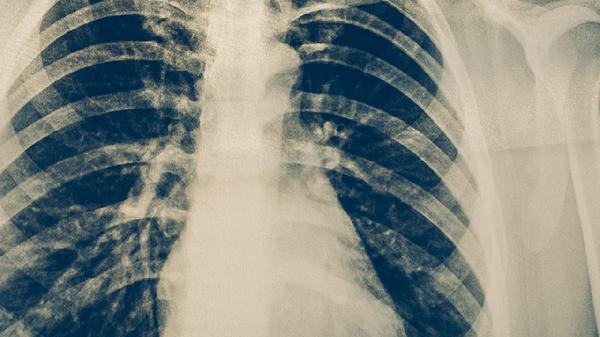

肺結(jié)核可通過(guò)生活干預(yù)、藥物治療、手術(shù)治療等方式治療。肺結(jié)核通常由結(jié)核分枝桿菌感染引起,主要表現(xiàn)為咳嗽、咳痰、發(fā)熱、盜汗等癥狀。

肺結(jié)核患者需嚴(yán)格遵醫(yī)囑完成全程治療,不可自行停藥。治療期間每月復(fù)查痰涂片和胸部X線,評(píng)估治療效果。注意與家人分餐,避免交叉感染。適當(dāng)進(jìn)行呼吸功能鍛煉,如腹式呼吸、縮唇呼吸等,有助于改善肺功能。出現(xiàn)咯血、呼吸困難等癥狀時(shí)需立即就醫(yī)。